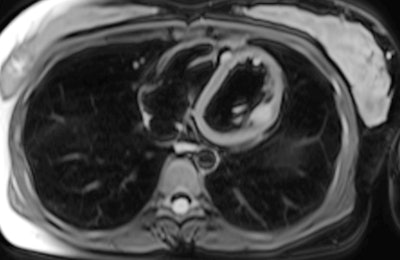

"Chest CT demonstrates poor sensitivity for detection of cardiac metastasis, with cardiac MRI performing much better. Still, neither CT nor MRI is as sensitive as [gallium-68 (Ga-68)] DOTATATE PET/CT for detection of neuroendocrine cardiac metastasis," noted Dr. John Renfrew and colleagues from the Mayo Clinic in Phoenix, Arizona, U.S.

Of the 26 cases, 17 also underwent a contemporaneous chest CT exam. Only one of these CT scans demonstrated evidence of neuroendocrine cardiac metastasis, Renfrew and colleagues reported.

Five of the 26 patients also received a contemporaneous cardiac MRI. Four of these scans correctly identified cardiac neuroendocrine involvement.